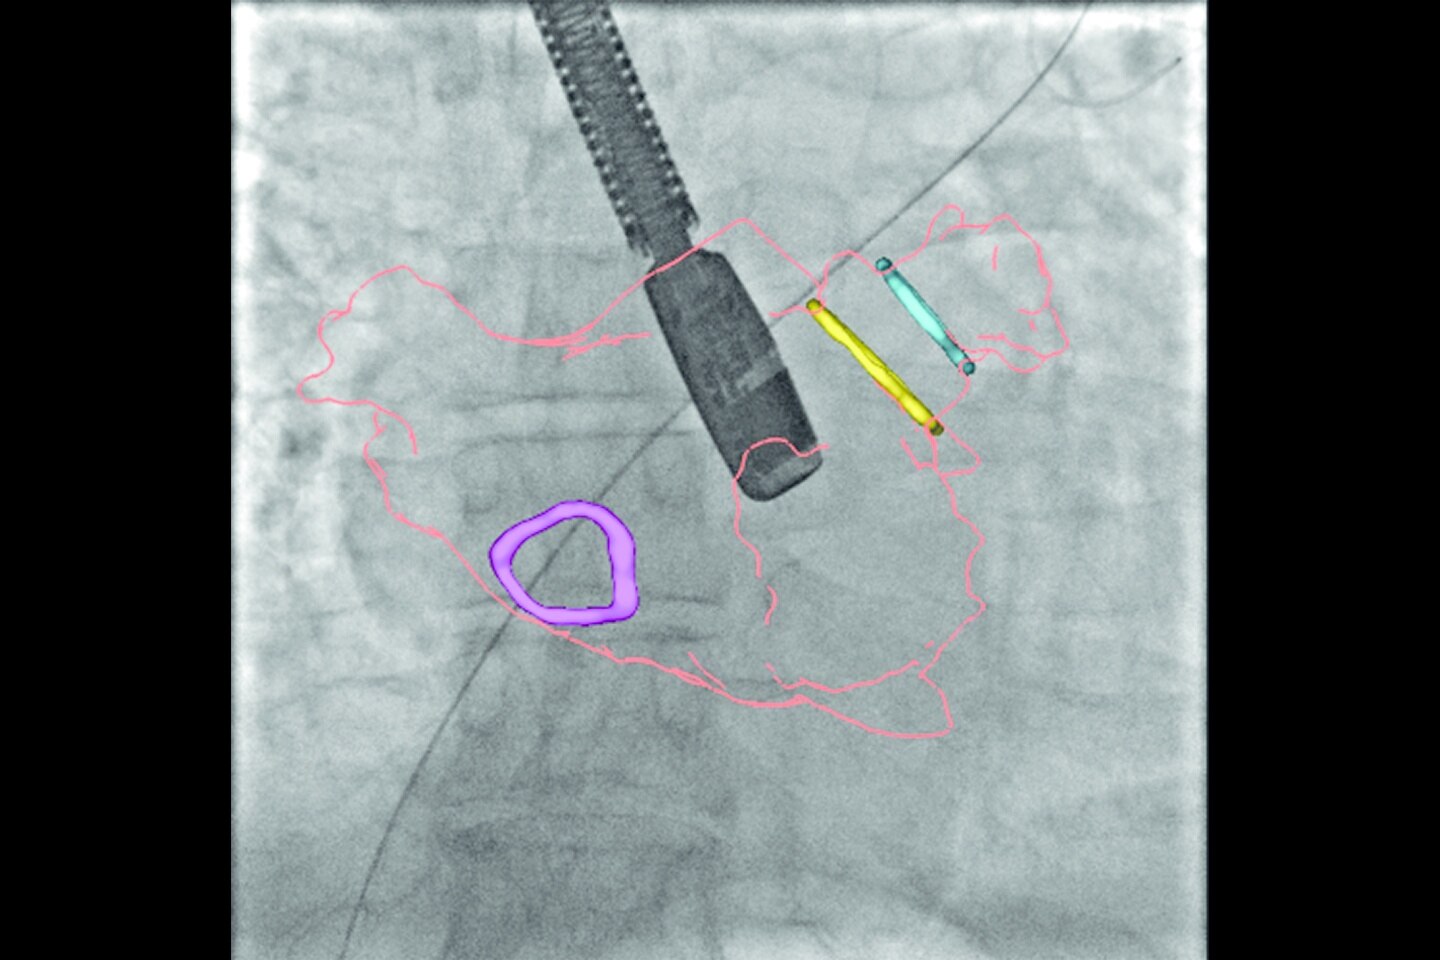

Birden fazla uygulamada çok yönlülük

Revolution Ascend; rutin, kardiyak, büyük bedenli hasta, Acil Servis ve girişimsel dahil olmak üzere çoğu ortama yönelik özelliklere sahiptir.